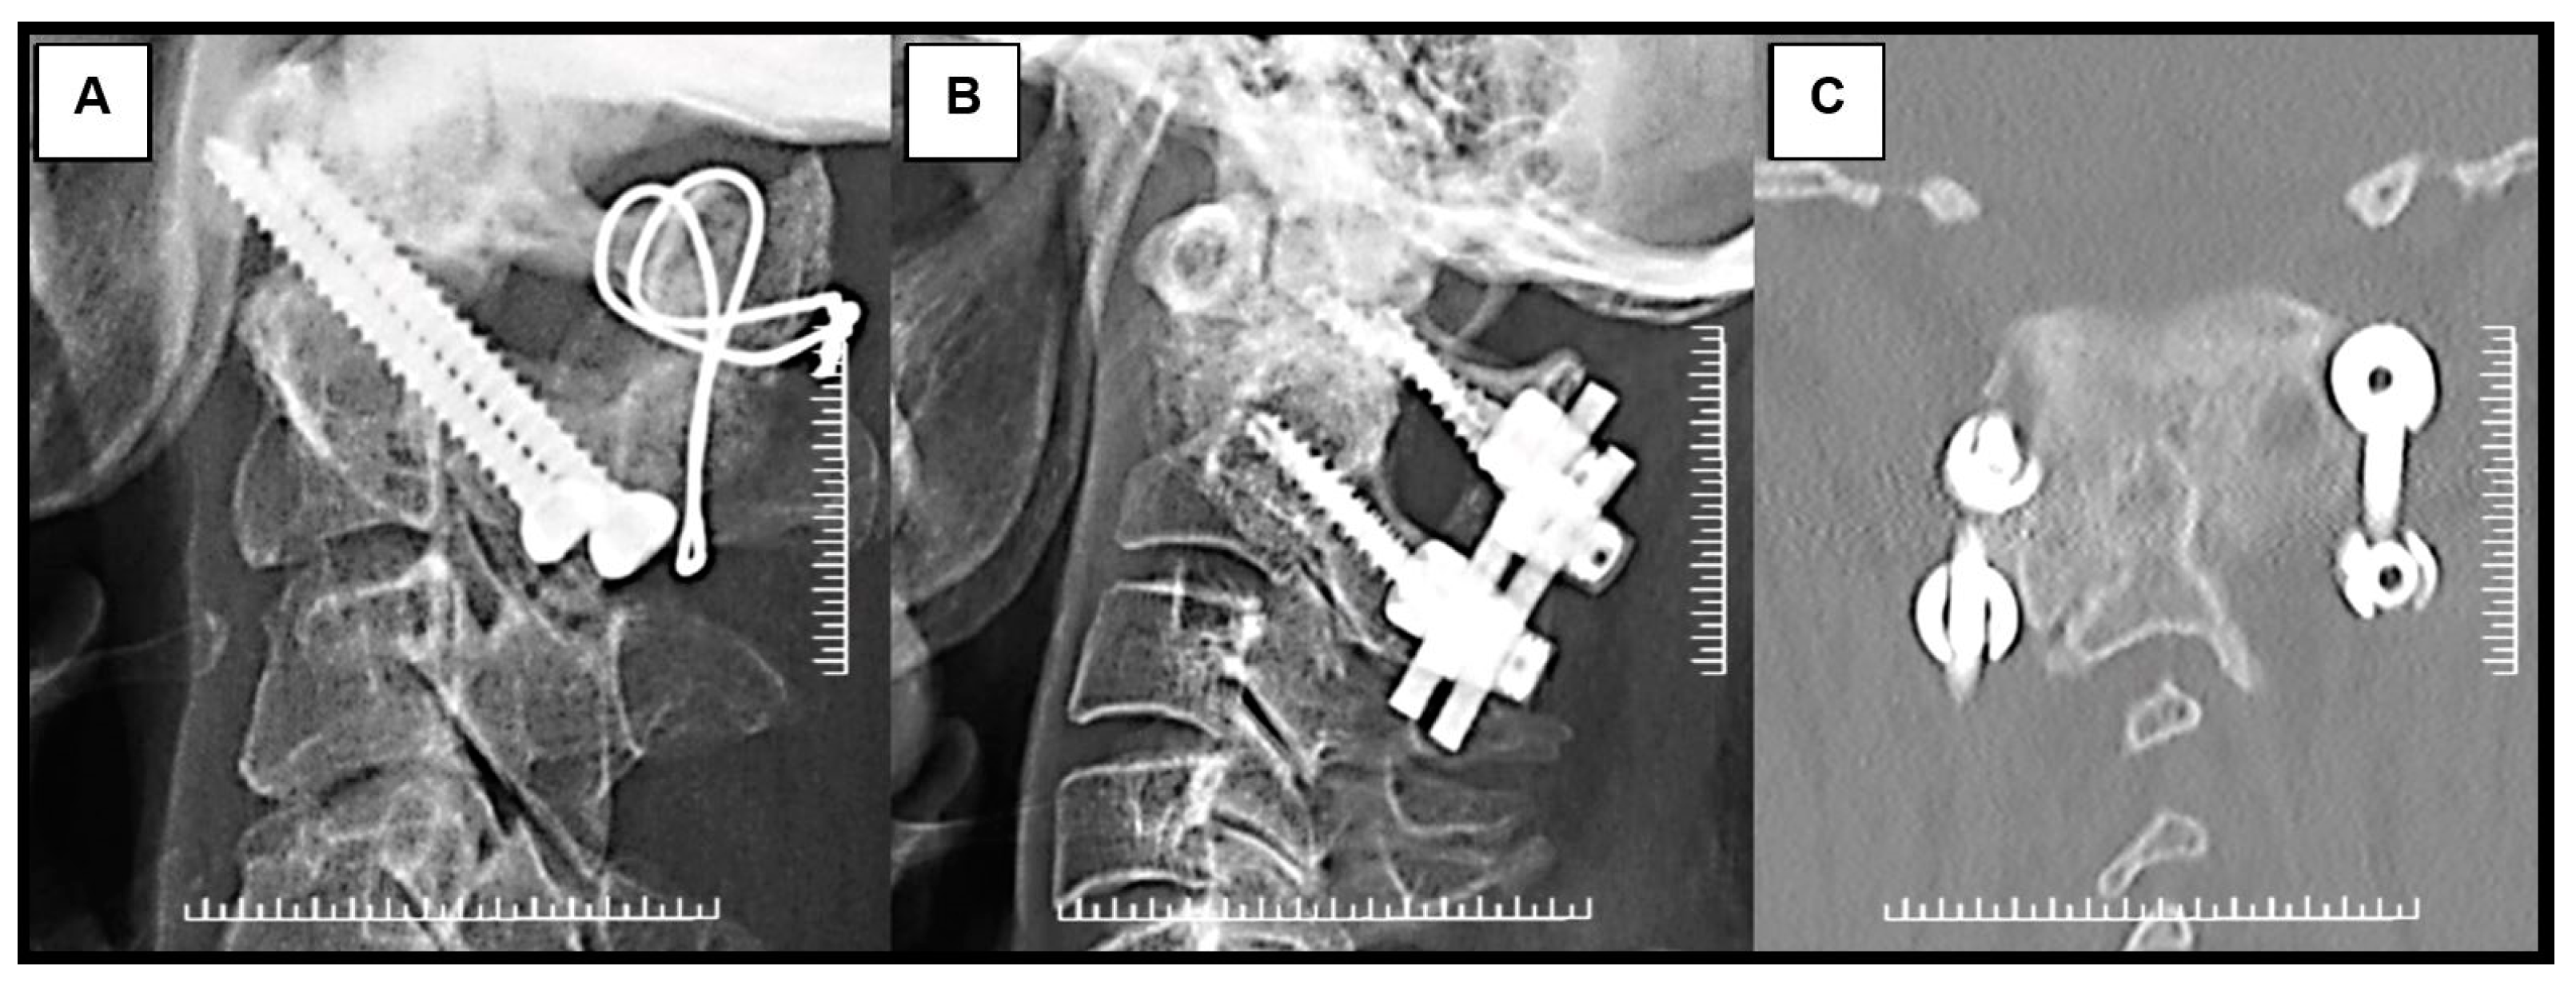

Before surgery, all patients had a standard series of radiographs, including the open mouth, anterior-posterior, static lateral, and dynamic lateral flexion/extension views. The lateral flexion-extension view was used to evaluate the instability of the C1-C2 complex, including the possibility of reduction that could be achieved intraoperatively. Excessive C1-C2 translation and lateral atlantodental interval more than 3 mm generally caused instability. Thus, in this case, the fusion of C1-C2 joints should be carried out. Computed tomography (CT) scan and magnetic resonance imaging (MRI) were also performed to evaluate further the bony anatomy detail of the upper cervical spine, the spinal cord, and the vertebral artery status (Figure 1). In our institution, the type of surgical fixation, either Magerl’s C1-C2 transarticular screw fixation technique augmented with supplemental wiring or Harms-Goel C1-C2 screw-rod segmental fixation technique, was selected based on local management protocol, which considered the width of the C2 isthmus, the vertebral artery pathway, and the presence or absence of a kyphotic back. Magerl’s C1-C2 transarticular screw fixation technique would be chosen for patients with a C2 isthmus wider than 3.5 mm, absence of anomalous vertebral artery pathway, and no kyphotic back. Harms-Goel C1-C2 screw-rod segmental fixation technique was performed in the rest of the patients who were not indicated for Magerl’s C1-C2 transarticular screw fixation technique (Figure 2).

Figure 3. Radiographic images of patients with reducible nonunited type II odontoid fracture with myelopathy treated with (A) Magerl’s C1-C2 transarticular screw fixation technique augmented with supplemental wiring and (B) Harms-Goel C1-C2 screw-rod segmental fixation technique. Coronal CT scan imaging (C) shows C1-C2 complex screw construction with solid fusion mass in Harms-Goel C1-C2 screw-rod segmental fixation technique at 3-month follow-up.